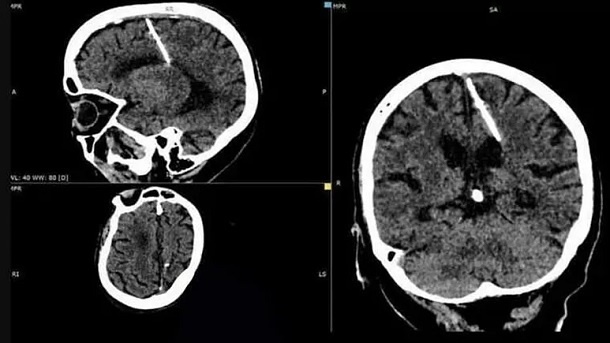

مقامات بهداشتی جزیره ساخالین در روسیه میگویند یک سوزن سه سانتیمتری را در مغز یک پیرزن ۸۰ ساله پیدا کردهاند.

رادیولوژیستهای درمانگاه در این جزیره این سوزن را در جریان انجام یک تصویربرداری اشعه ایکس از مغز این زن یافتهاند. پزشکان معتقدند این سوزن از زمان تولد این زن در مغز وی بوده و نشانهای است از این که احتمالا والدینش در دوره نوزادی قصد کشتن او را داشتهاند.

مطابق اعلام پزشکان سوزن در لوب جداری چپ مغز این زن جای گرفته است، با این حال از بیم اینکه عمل جراحی وضعیت او را بدتر کند آنها تصمیم گرفتهاند سوزن را برندارند.